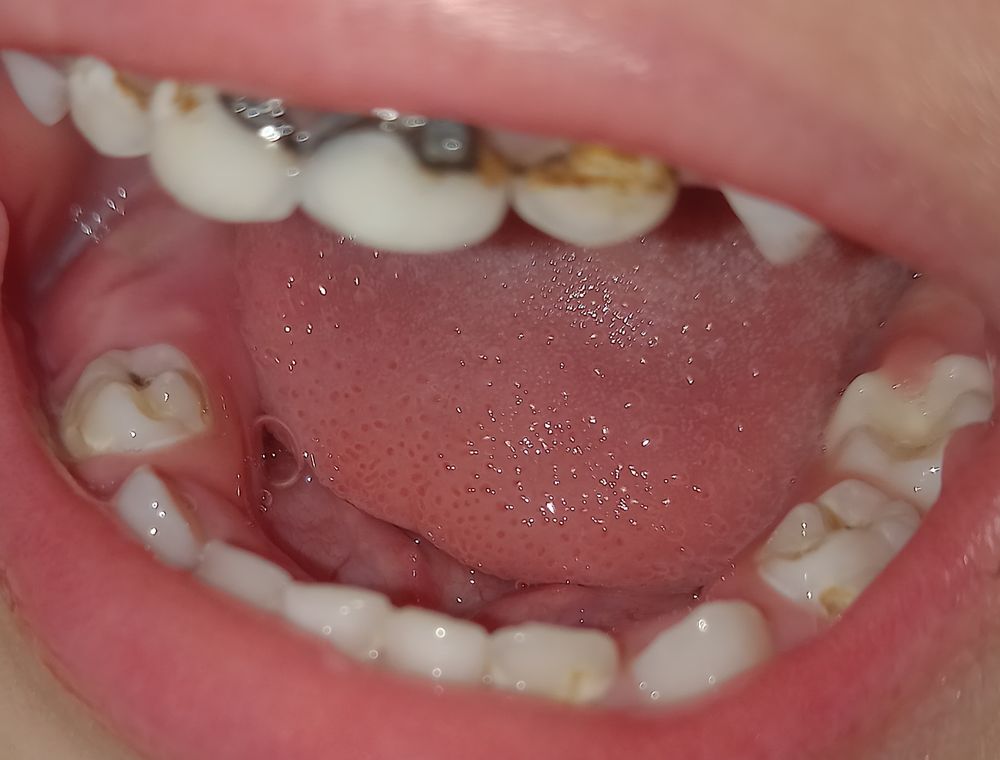

Юлия, вот купил щетку колгейт 2+ заяц. За 2 недели утром и вечером смог убрать налет с зуба и обнажилась полость с боку 4го зуба нижнего с обоих сторон челюсти у этих зубов. Что же делать ....